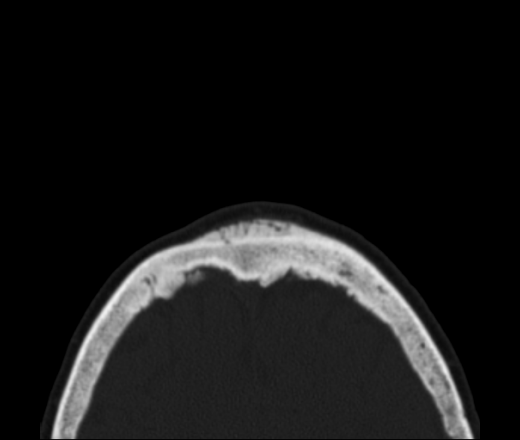

Какие аргументы будут? Ведь деструкции никакой нет. Изменения по типу реактивных. Просто анализирую для себя. Гиперостоз такой ни разу не стречал при такого рода сарком... Стенки пазухи клиновидной кости тоже изменены, утолщены. Коллеги, будут еще мнения?

При лобном гиперостозе изменения только по внутренней пластинке. Про менингеому можно почитать в книге Г.Ю.Коваль "Рентгенодиагностика заболеваний и повреждений черепа" (1984).

Вы правы, Марта, по внутренней, а здесь по обеим. Но мне кажется, что в любом случае это доброкачественное изменение...

Дайком залить не могу, нахожусь на другом рабочем месте уже... Про менингиому как-то не укладывается у меня... Внутренний кортикал не разрушен, но изменен.

Значит так, Сергей Николаевич, представьте исследование корректно: с полной клиникой, рентгенограммами, подробной серией КТ. Пока это "рак, сифилис и несчастная любовь". Есть мягкотканная масса в пазухах и полости носа, есть ли деструкция стенок - по этим сканам судить нельзя. Есть спикулообразный периостоз в лобной кости, который м.б. при десятке заболеваний: от серповидноклеточной анемиии до остеосаркомы или мтс. Есть ли связь между этими изменениями - по тому, что вы показали - не видно.

Спасибо за ответы, все принял к сведению. Про Педжета подумал сразу, когда открыл серию, но почему-то, почитав и посмотрев библиотеку случаев отверг...

Я, за "педжетовские происки"...